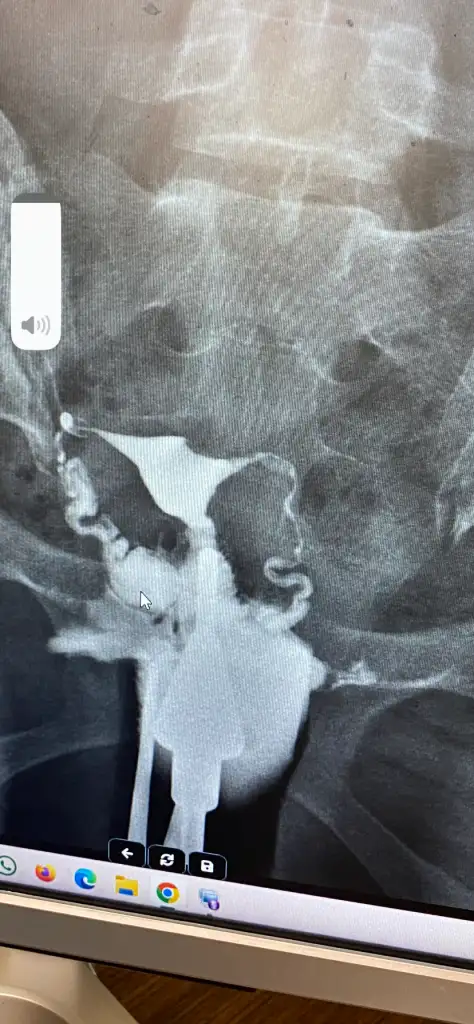

Kaldığım memleket te tüp bebek merkezi yok maalesef büyük şehirlere gitmem gerekecek ameliyatı nerede oldunuz tüp bebek merkezinde mi hastanede miEki Görüntüle 3516210 Bakın benim rahim filmim de böyleydi. Doktorum gayet güzel planlamayı yaptı, ben de uydum. Gayet de mutluyum. Şimdi transfer sonucumu bekliyorum. Bir tüp bebek doktoru bulun kendinize, daha fazla üzülmeyin sürecinize başlayın. Geçmiş olsun.

Eki Görüntüle 3516210 Bakın benim rahim filmim de böyleydi. Doktorum gayet güzel planlamayı yaptı, ben de uydum. Gayet de mutluyum. Şimdi transfer sonucumu bekliyorum. Bir tüp bebek doktoru bulun kendinize, daha fazla üzülmeyin sürecinize başlayın. Geçmiş olsun.